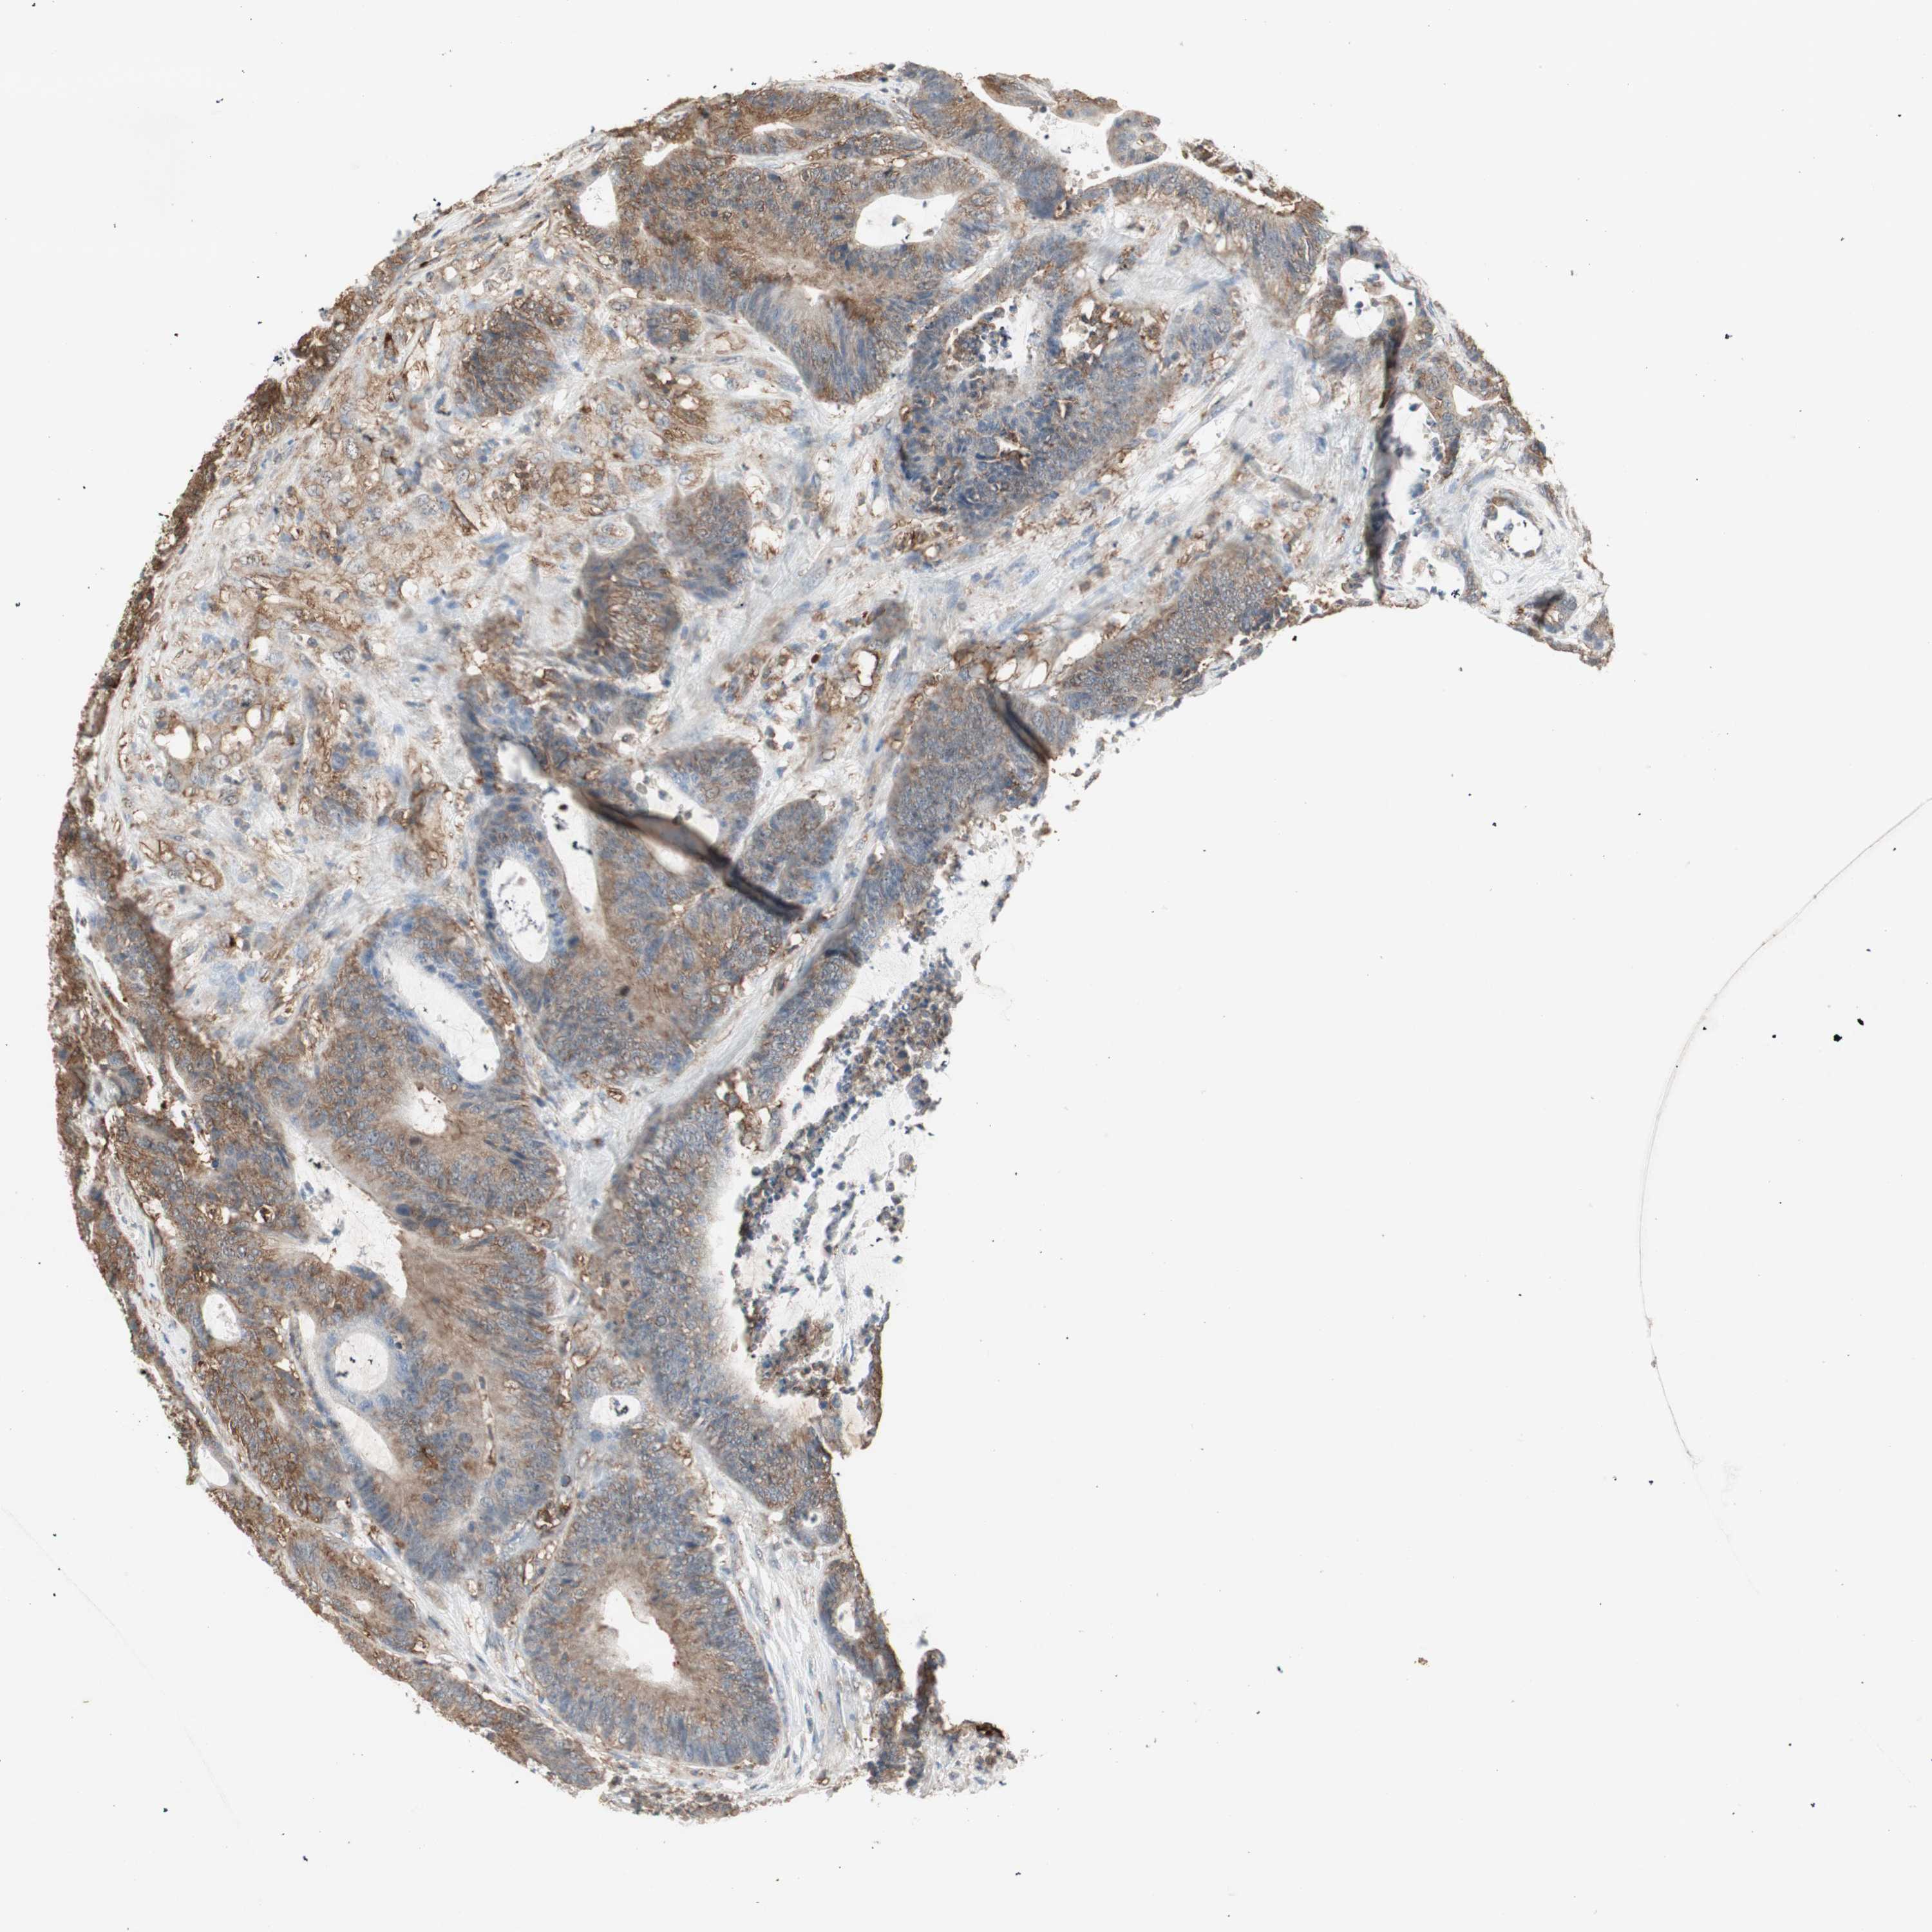

CANCER COLORECTAL CANCER Show tissue menu

Colorectal cancer

Human cancer

Colon adenocarcinoma

Rectum adenocarcinoma